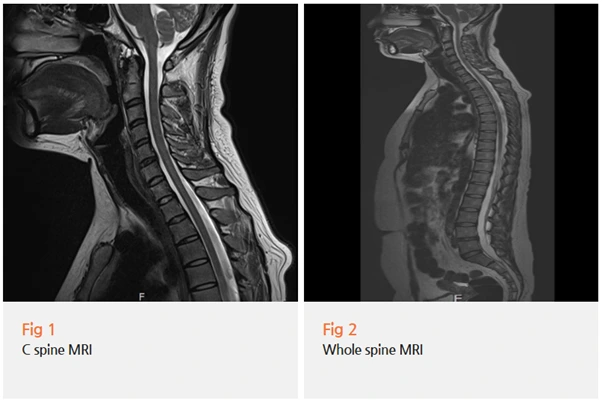

그래서 당일 근전도 검사와 경추 MRI를 먼저 시행했습니다.

다행히 기질적인 신경 손상이나 구조적인 이상은 발견되지 않았어요.